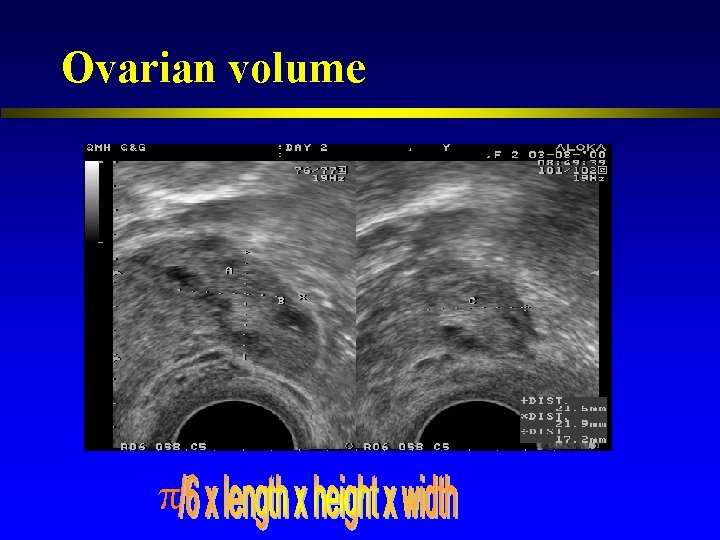

Ovarian volume

Ovarian volume l Total ovarian volume and the volume of the smallest ovary predictive of peak E 2 levels, no. of oocytes and cycle cancellation (Syrop et al. , 1995) l Mean ovarian volume prior to stimulation predictive of poor ovarian response (Lass et al. , 1997)